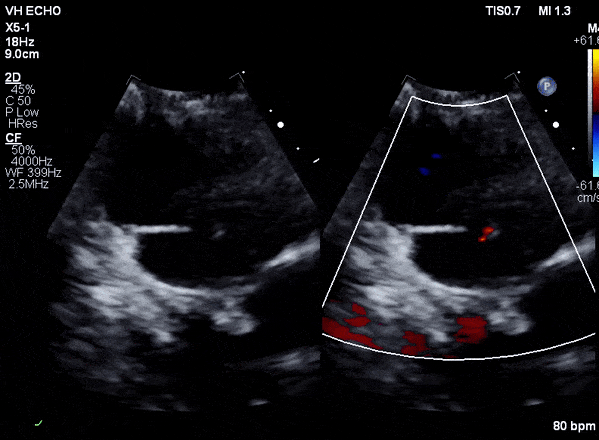

Case 2 (Pulmonic Valve IE)

Case 3